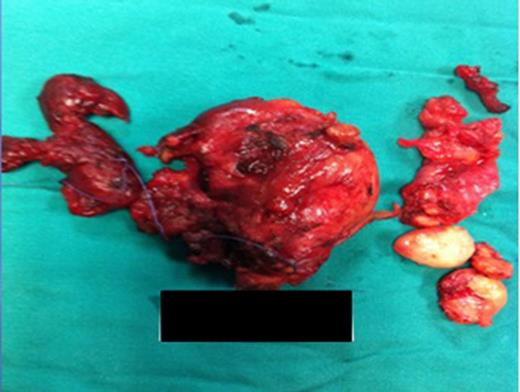

Surgical specimen: thyroid gland with an enlarged left lobe (retrosternal extension).